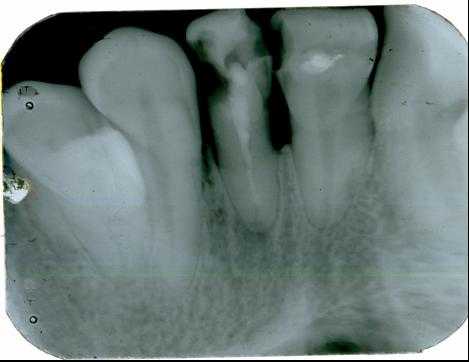

- измерительный снимок — снимок зуба на этапе лечения с введенными в каналы эндодонтическими инструментами с фиксированной стоппером длиной рабочей части или верификаторами после инструментальной обработки каналов. Если ортогональная проекция выполнена корректно, при условии точной калибровки программы визиографа и отсутствии проекционного искажения для резцов и премоляров некоторые измерения могут быть проведены по диагностической радиограмме. Для многокорневых зубов предпочтительно измерение длины каналов с помощью эндодонтических инструментов (рис. 1) , апекслокатора или по трехмерному снимку.

- контрольный снимок делается непосредственно после окончания эндодонтического лечения с целью определить, насколько качественно запломбированы корневые каналы, а также через определенное заданное время, дабы удостовериться в отсутствии или выявить наличие осложнений (рис. 2) . При исследовании многокорневых зубов и в случаях, когда имеется дополнительный канал, на снимке, выполненном с орторадиальным направлением луча (прямая проекция), корневые каналы часто накладываются друг на друга, что значительно затрудняет диагностику и может привести к ошибке в процессе лечения. Для получения раздельного изображения корневых каналов используется радиография с косым (эксцентрическим) направлением центрального луча (рис. 1) . Применительно к каждому конкретному случаю выбирается мезиальный или дистальный наклон (ангуляция) тубуса в горизонтальной плоскости (подробнее см.: Рогацкин Д. В., Гинали Н. В. Искусство рентгенографии зубов, 2007).

В идеале максимум информации о топографии корней и состоянии тканей периодонта может быть получен при проведении полипозиционной радиографии. В данном случае с диагностической целью делается три снимка — один в прямой, с орторадиальным направлением луча, и два в косой проекции — с дистально-эксцентрическим (рис. 1) и мезиально-эксцентрическим направлением луча (соответственно, прямая, задняя косая и передняя косая проекции).

Важнейшими аспектами успешной внутриротовой радиографии являются стандартизация и последовательная коррекция манипуляций. Под стандартизацией манипуляций подразумевается способность специалиста, проводящего лучевое исследование, выбрать оптимальный для каждого случая метод и сделать серию идентичных снимков вне зависимости от положения, состояния пациента и времени, отделяющего одно исследование от другого. То есть, если диагностический или измерительный снимок признан качественным, каждый последующий уточняющий и контрольный должны быть сделаны с теми же пространственными и техническими установками и каждое последующее изображение должно быть идентично предыдущему (рис. 1, 2) .

Рис. 1. Диагностический и измерительный снимки зуба 36, выполненные в прямой (а) и дистально-эксцентрической проекции (б). 36 — хронический апикальный периодонтит (К04.5) с характерными изменениями на мезиальном корне.

Рис. 2. Контрольный снимок непосредственно после лечения зубов 21, 22 (хронический периапикальный абсцесс в состоянии нагноения) (а) и отсроченный контрольный снимок через 5 месяцев после пломбирования канала (б), состояние репарации на этапе лечения.